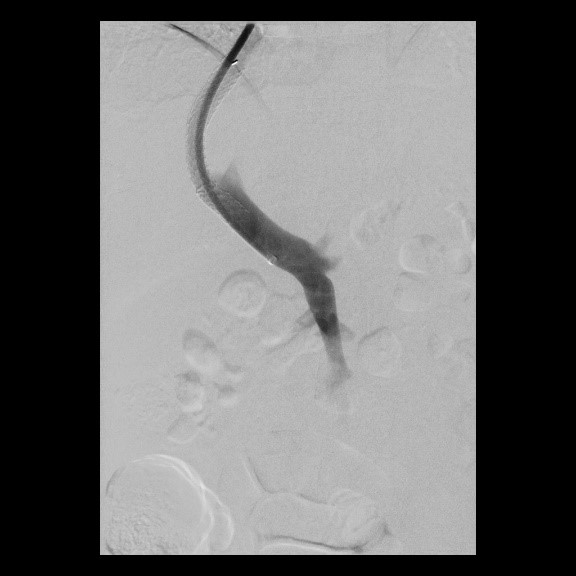

Implantation eines Port-Systems über die rechte innere Drosselvene (V. jugularis interna dextra)

(Bild 1 von 4)

Erfolgreiche Implantation eines transjugulären intrahepatischen portosystemischen Shunts (TIPSS) bei Leberzirrhose und refraktärem Aszites. Darstellung der Lebervenen

(Bild 2 von 4)